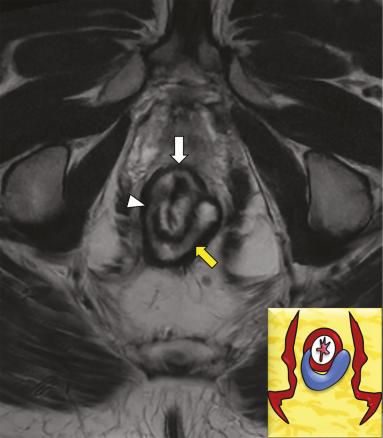

Maladie de Crohn chez un patient âgé de 67 ans avec lésions anopérinéales. Image axiale en pondération T2 d’une IRM anopérinéale à la hauteur du bas rectum (flèche blanche) montrant un trajet fistuleux en fer à cheval (flèche jaune) alimenté par un orifice interne rectal latéral droit (tête de flèche), anomalie difficilement perceptible à l’examen clinique.